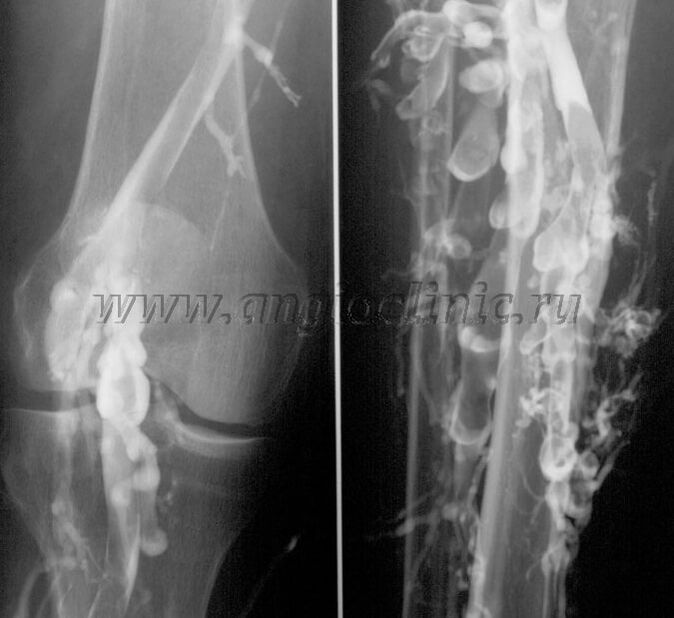

Venografía de contraste

Por lo general, la ecografía es suficiente para un diagnóstico completo de patología venosa, pero en algunos casos es necesario estudiar la relación entre el estado del sistema venoso profundo y superficial, especialmente en caso de recaídas de varices y venas varicosas secundarias.

Para resolver estos problemas, se utiliza un examen de rayos X con contraste. Se perforan las venas safenas y se administra contraste. El movimiento del contraste se observa en el monitor del aparato de rayos X y se realizan todas las pruebas y proyecciones necesarias. Actualmente, la venografía para las venas varicosas se utiliza muy raramente.